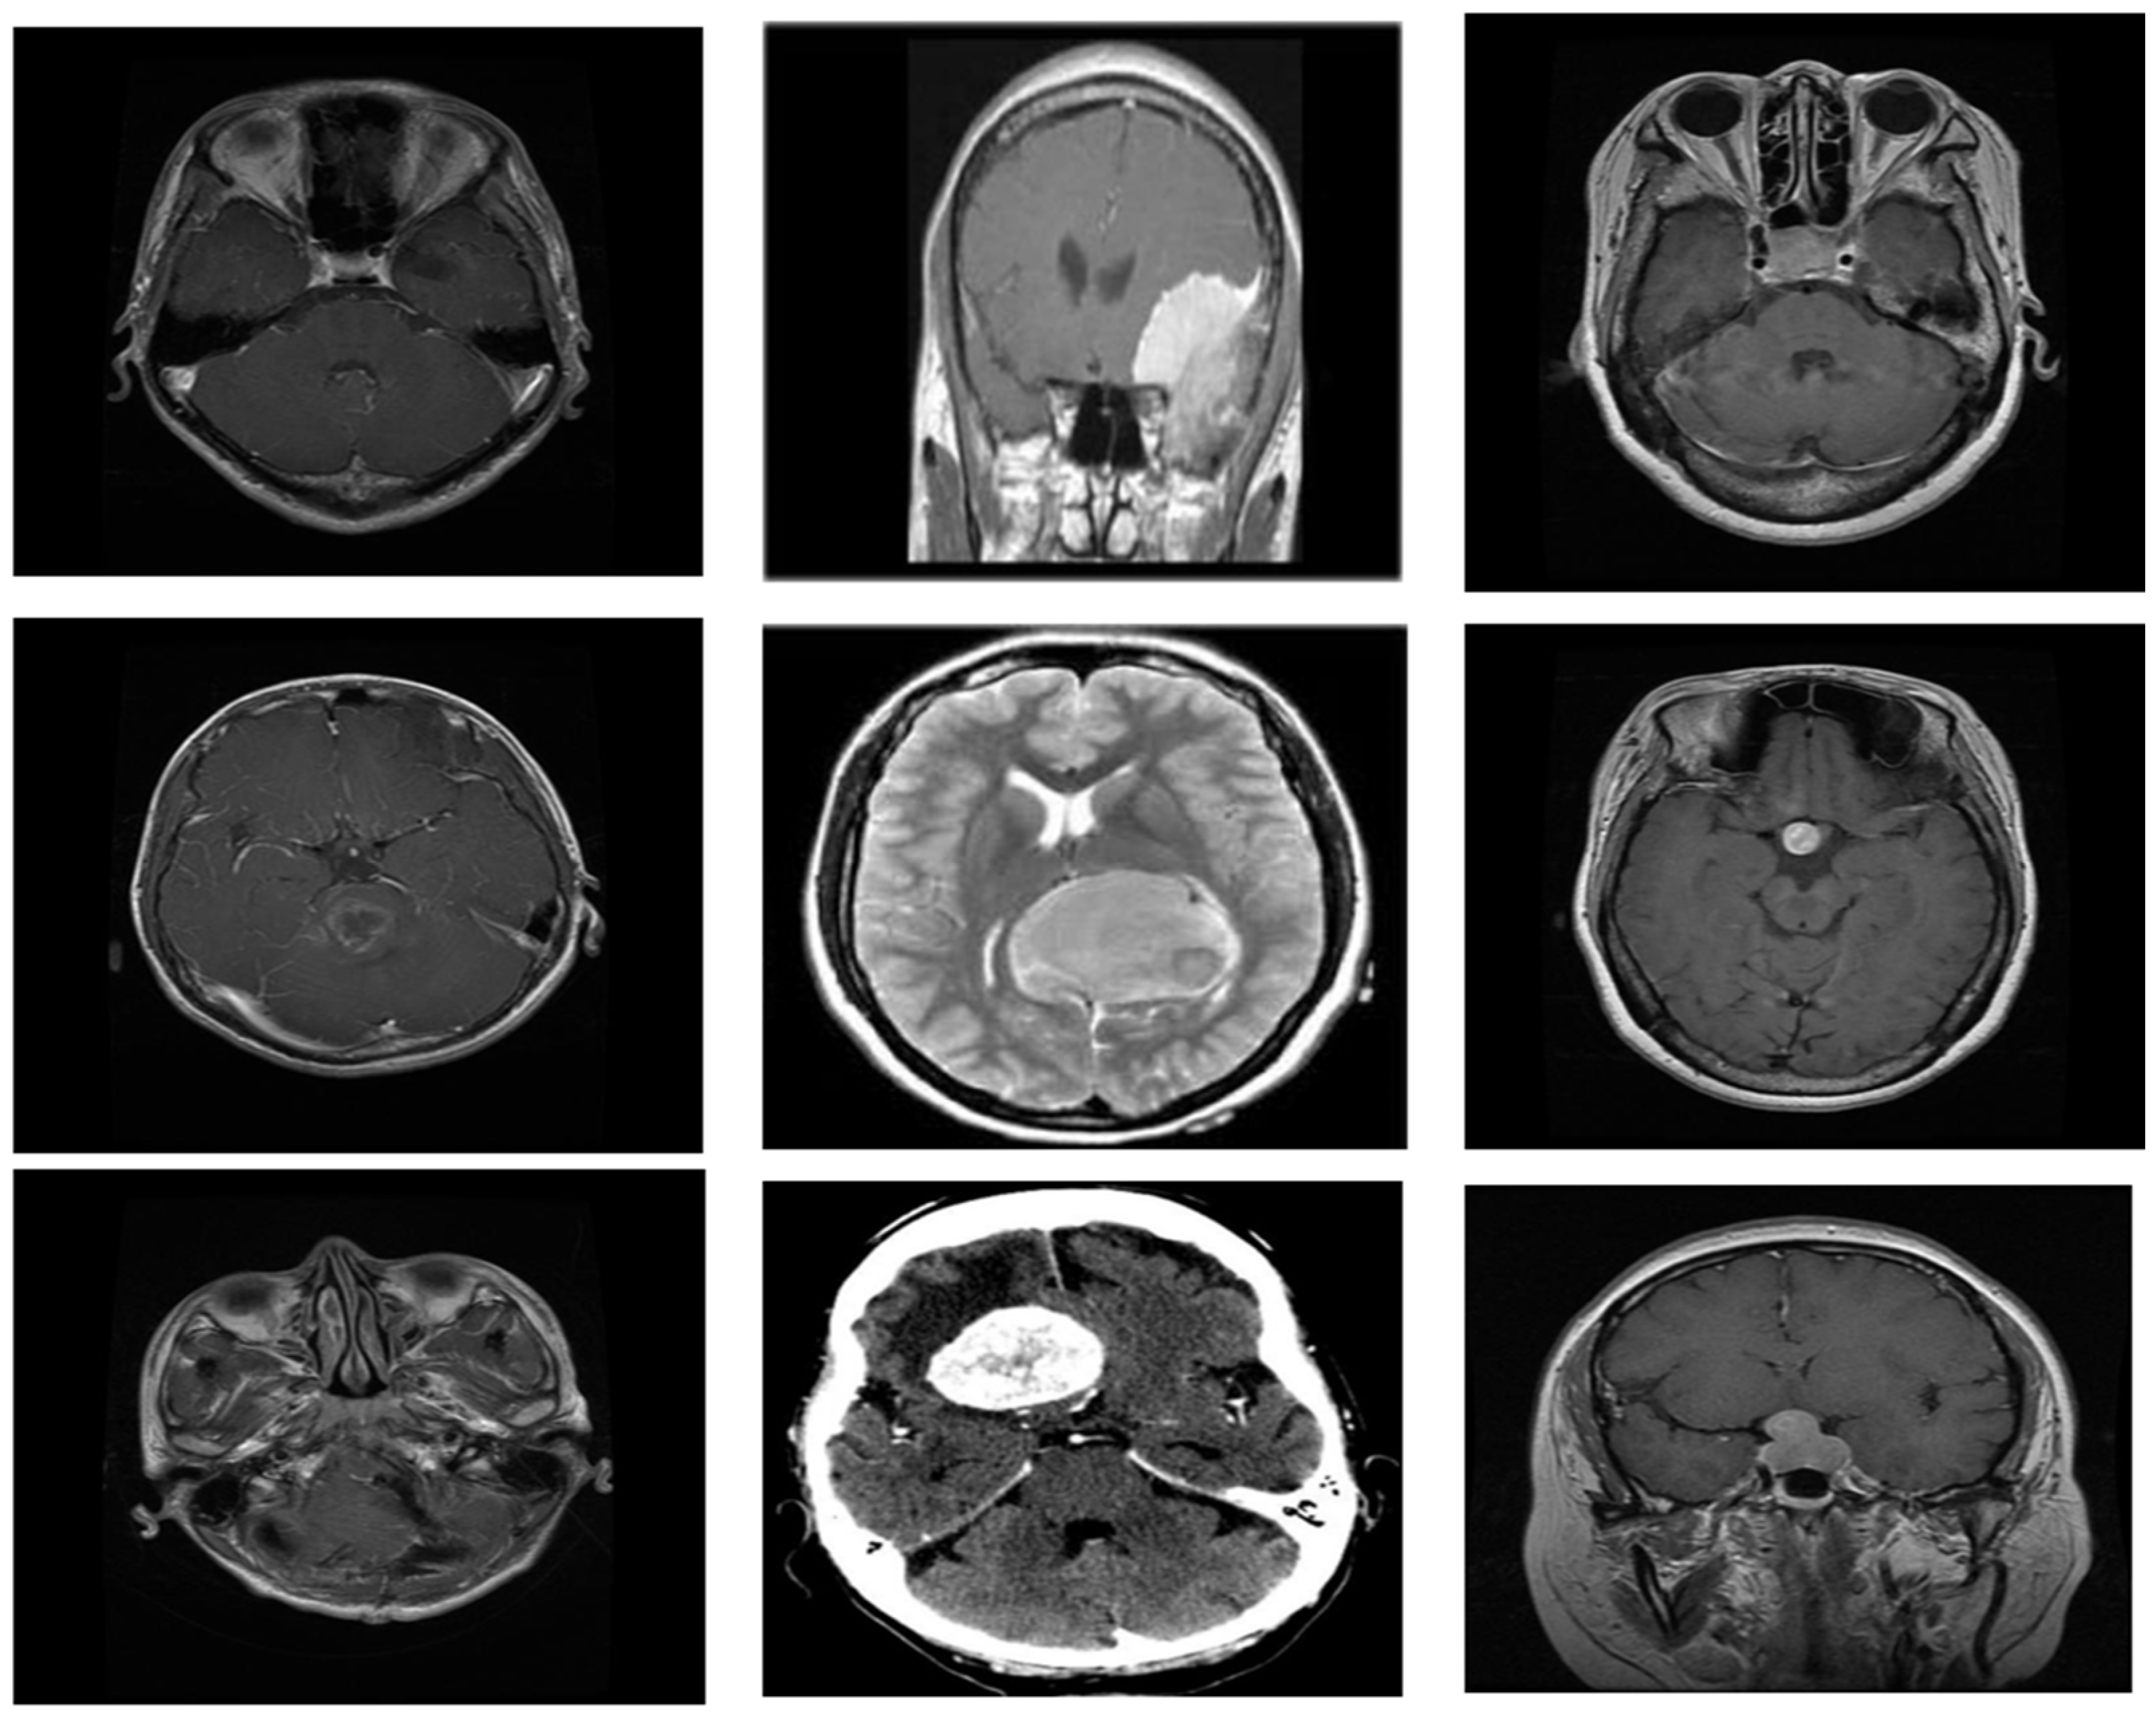

3. Materials and Methods

- (a)

- Glioma:

- (b)

- Meningioma:

- (c)

- Pituitary: